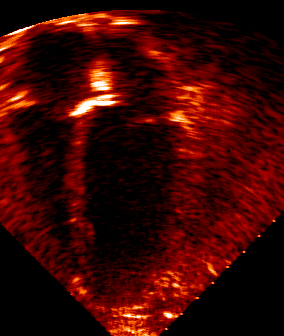

The filtered image. Wavelet scales 4 and 5 were retained, and here we see the sum of these two images.

The image in FITS format (32-bit real) was wavelet transformed (à trous method), mr_transform -n 6 -x echoc.fits echocard , and the output images translated to GIF in IDL.